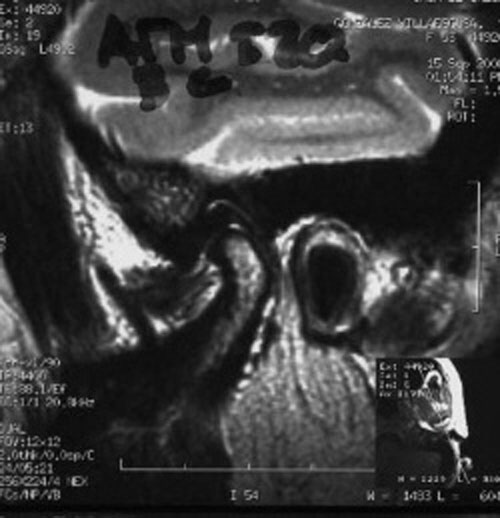

RMN de ATMs (17-09-2008): Dentro de la normalidad.

– ATMs dentro de la normalidad.

PRUEBAS DIAGNOSTICAS COMPLEMENTARIAS: